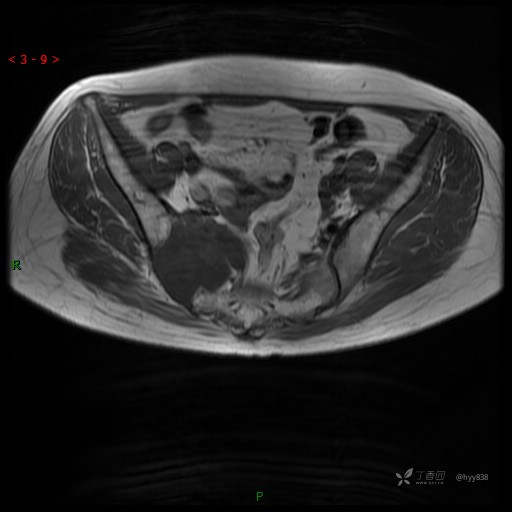

MRI平扫(axi T1WI+T2WI-fs)